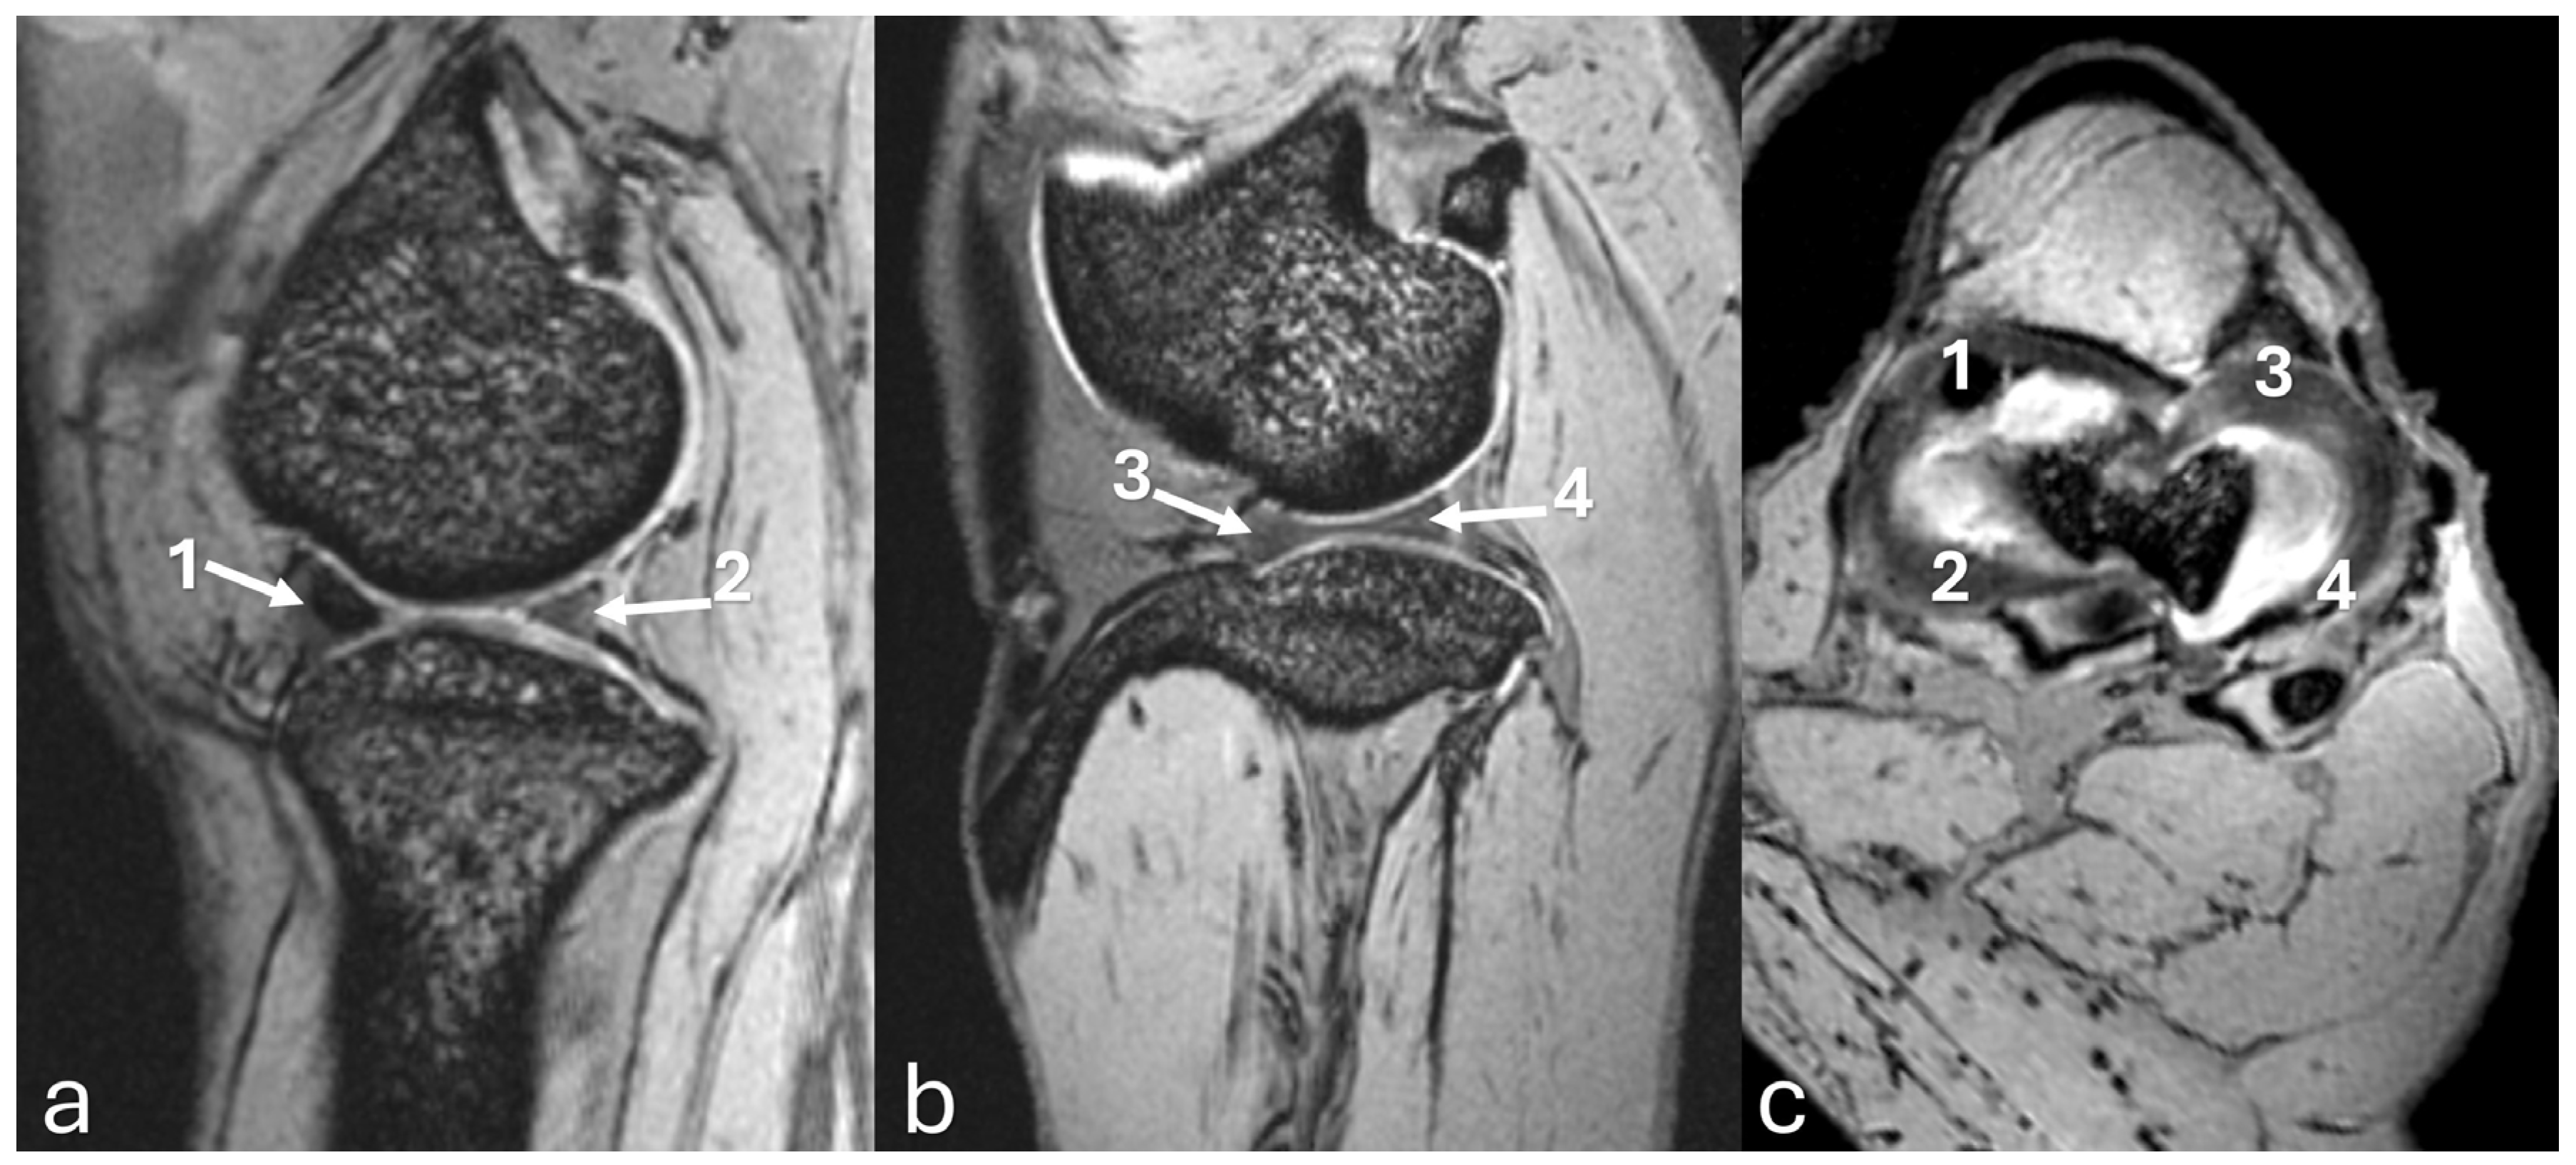

3.2. Stifle Joint Description